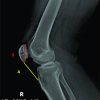

For a successful scaphoid surgery, a few key technical steps are crucial: achieving a precise entry point, ensuring that the guide wire is placed accurately along the central axis of the scaphoid in both antero-posterior [Fig. 6,7] and Lateral Views [Fig. 8,9] for optimal trajectory, and then carefully drilling over the guide wire followed by the correct placement of the Herbert screw along the same path[Fig. 10]. Each step demands meticulous execution to ensure proper compression, stability, and ultimately, a good functional outcome.

Insertion of the guide wire following the markings drawn to get a central trajectory. To be confirmed in both anterior–posterior and lateral views.[Fig. 6-9]